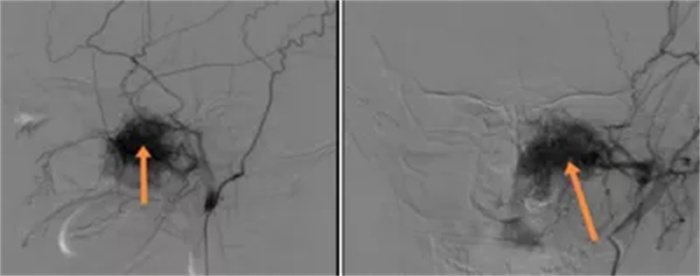

为确保手术顺利进行,专家们充分讨论并制定了术前诊治方案。手术当日,在主任医师冯俊、彭涛的指导下,杜经纬团队完整剥离了病变组织,保留了重要结构,顺利经鼻内窥镜鼻腔及唇龈沟联合径路完整切除肿瘤,患者术后转入重症监护室观察。

在耳鼻咽喉头颈外科精心治疗下,该名患者恢复良好,术后第一天即转回普通病房,现已痊愈出院。